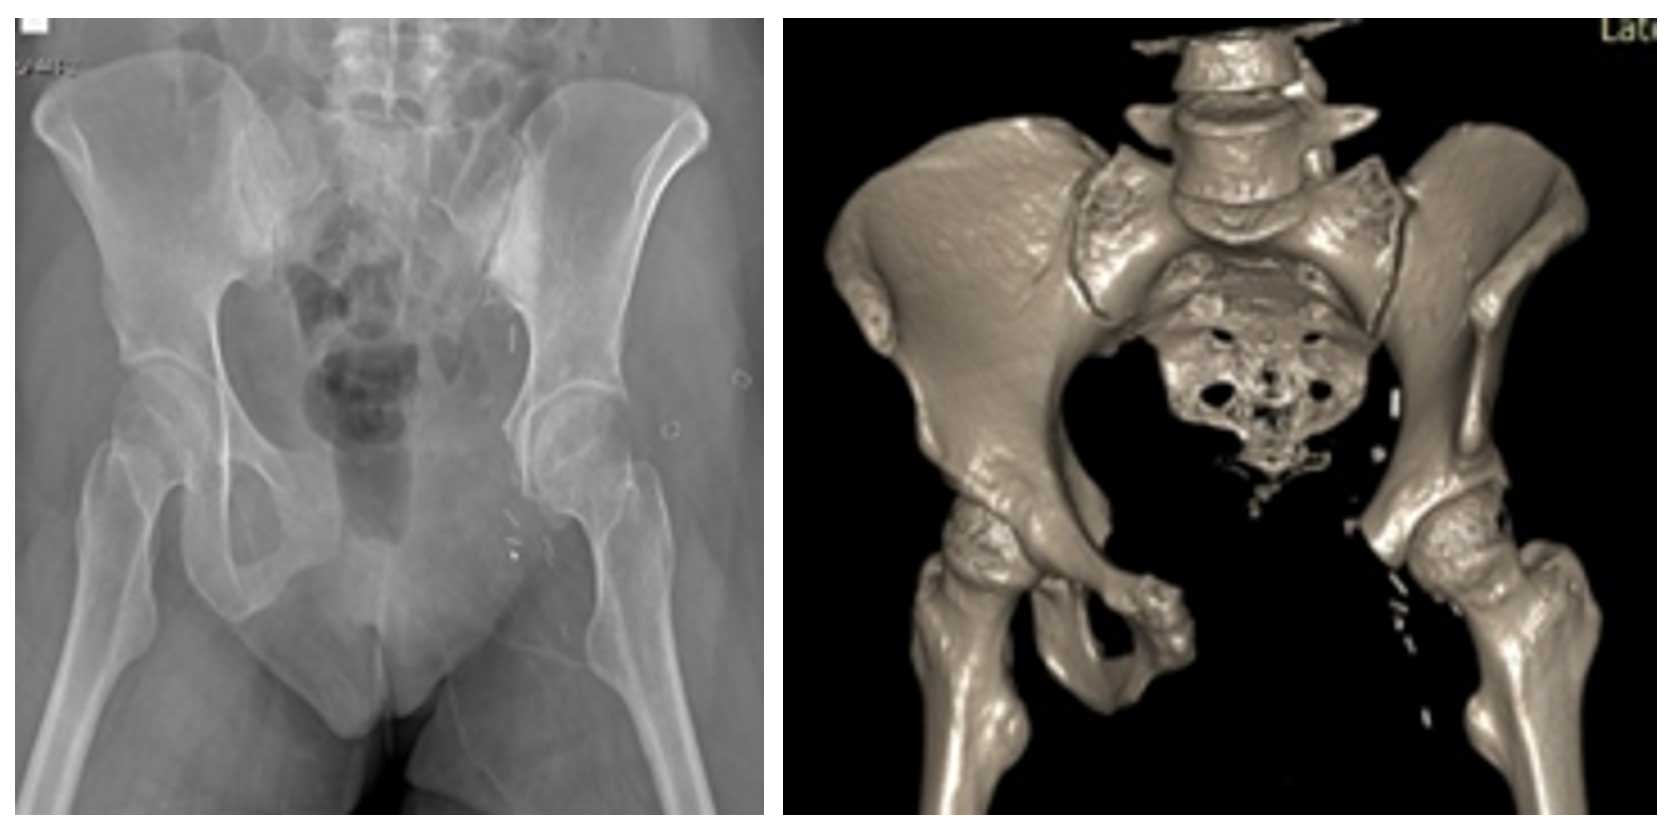

Ameliyat Öncesi: Röntgende sol pubik kolda düzensizlik ve sklerotik tümör dokusu görülmekte.

Ameliyat Sonrası: Röntgen ve tomografide rezeksiyon sonrası görülmekte.